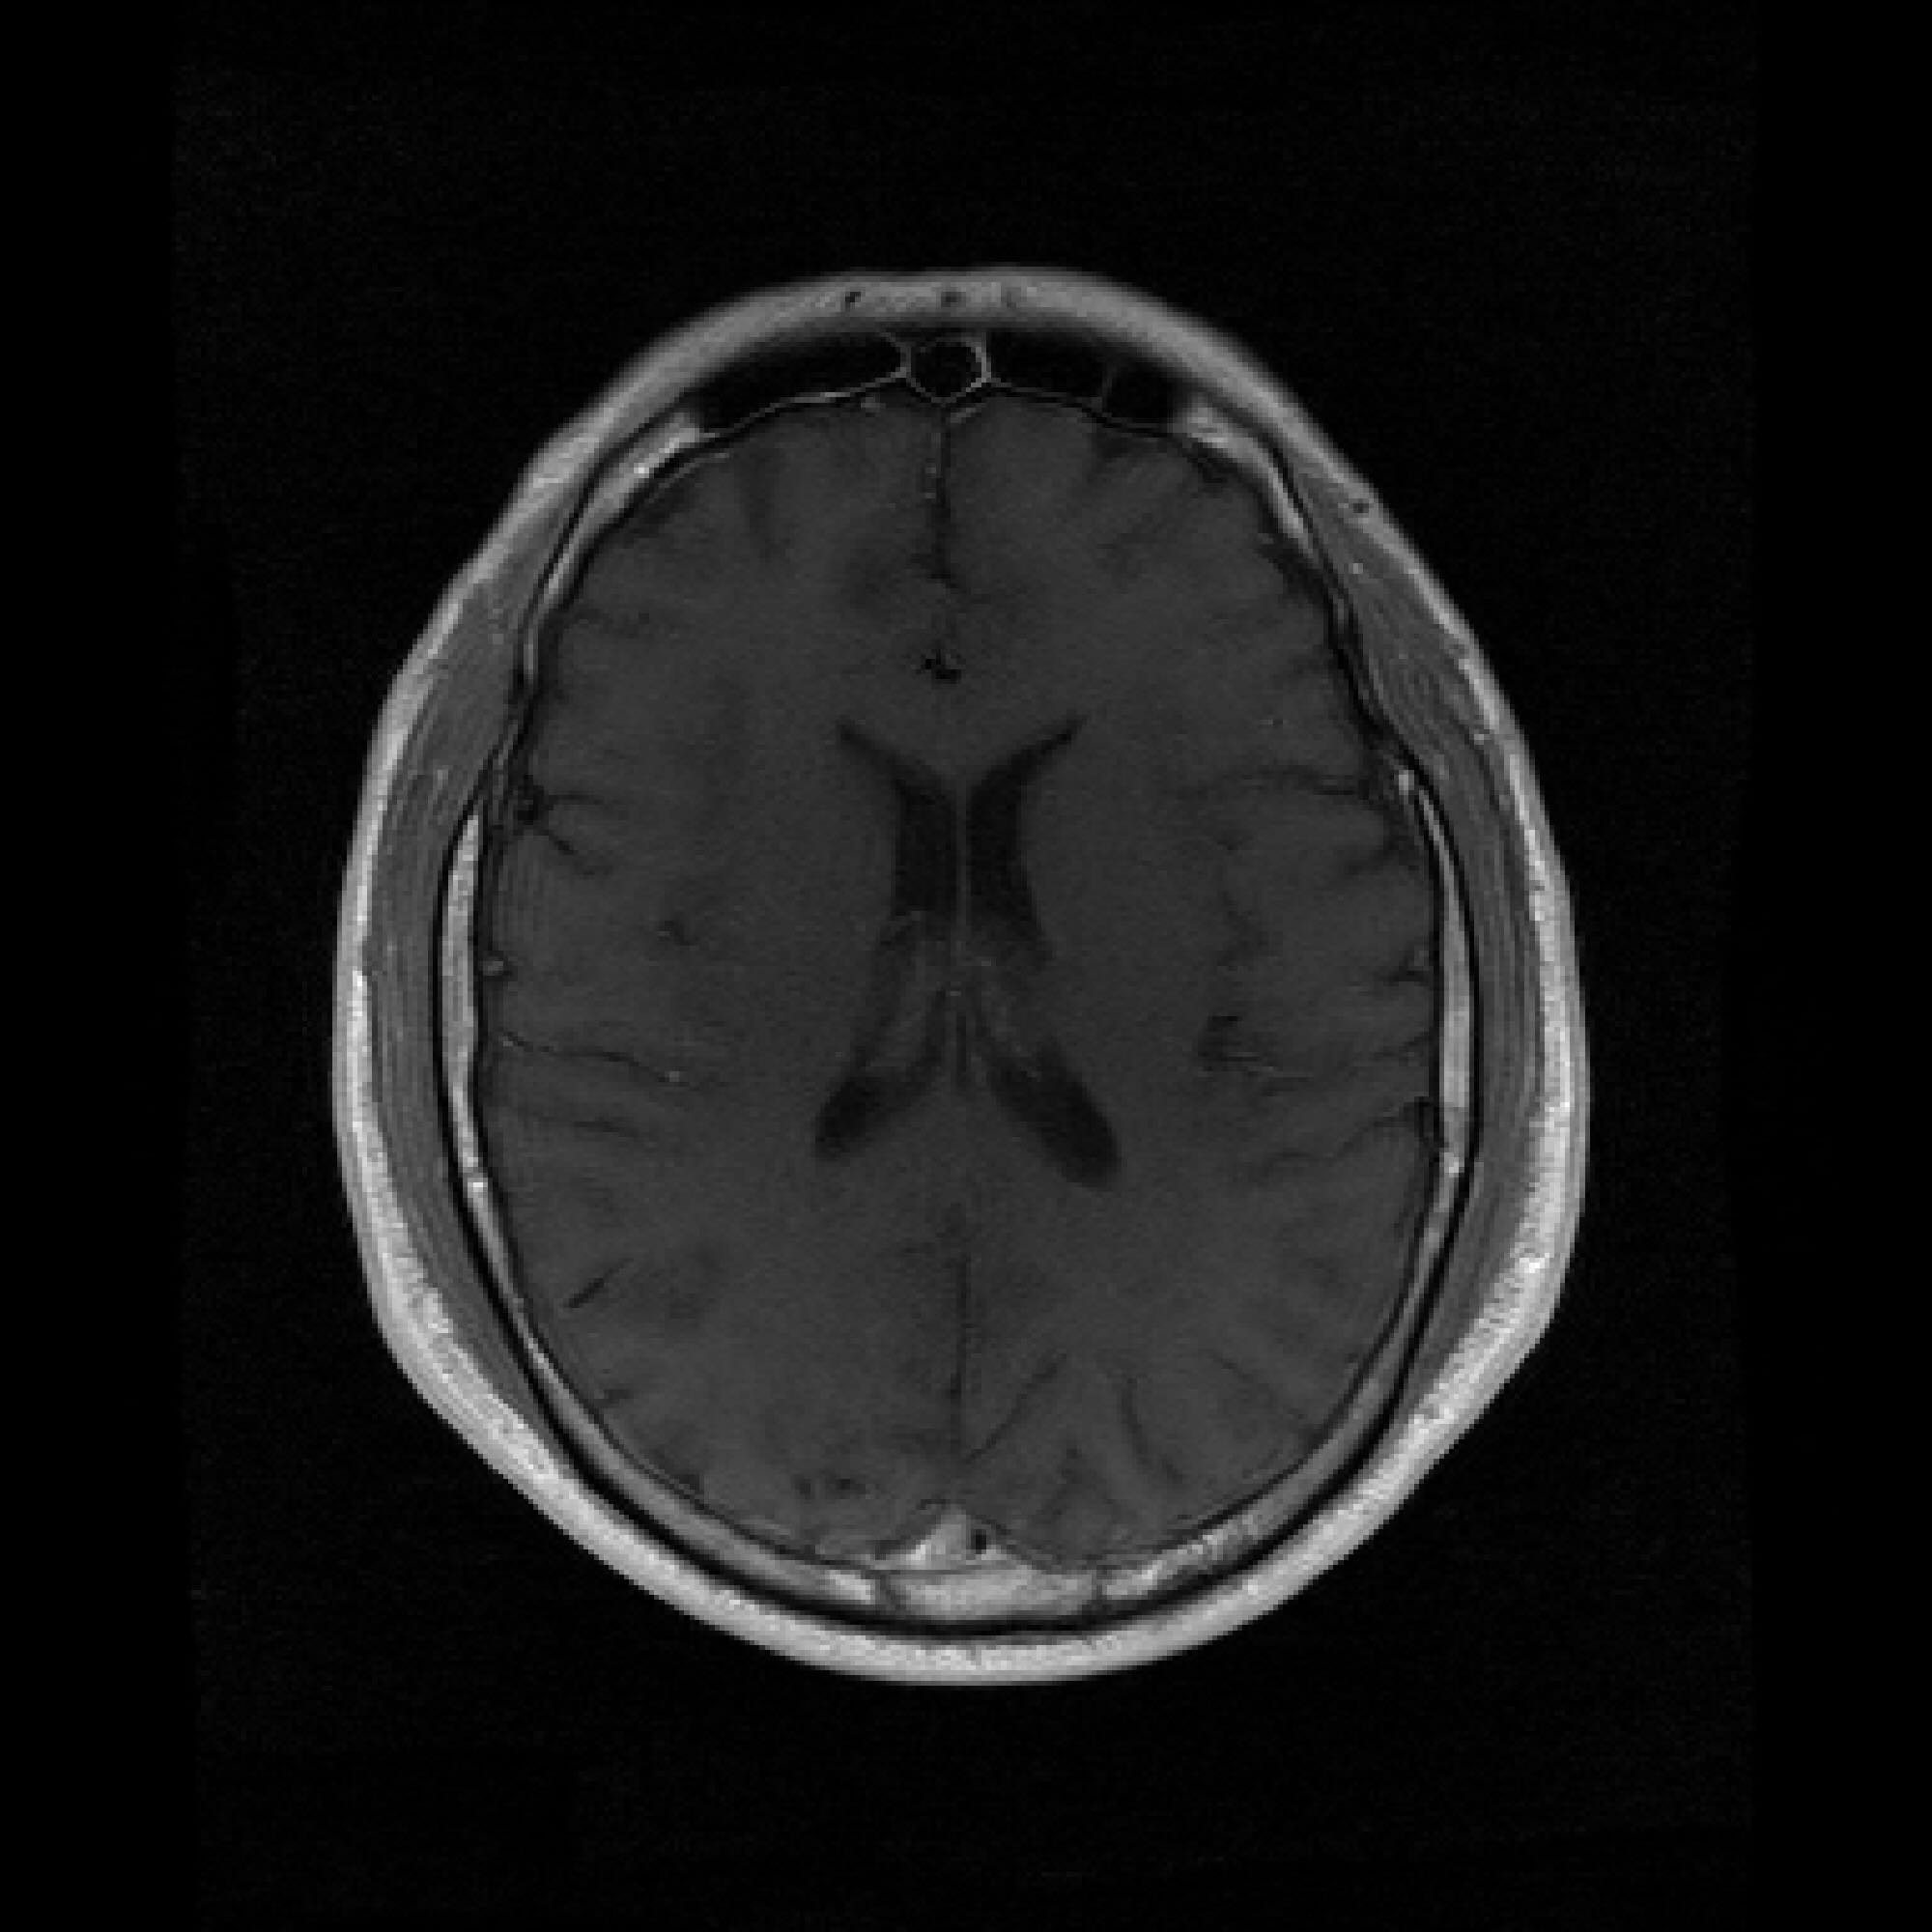

B.3 Unconditional Generation Quality

Figure 5 shows sampled unconditional generations for both PaDIS-MRI and FastMRI-EDM, at model convergence. As discussed previously, we trained models by qualitatively evaluating the change in unconditional generation quality over time. The FastMRI-EDM model is able to capture more detailed anatomy in its unconditional generations, whereas PaDIS-MRI tends to generate more uniformly gray ovals with limited detail. We hypothesize that the relatively poorer-looking unconditional generations of PaDIS-MRI may actually make it more robust during inference, or conditional generation. Rather than capturing intricate global features, the relatively simple structure may provide a form of implicit regularization that favors locally consistent features over potentially spurious or overfitted global patterns.

Figure 5: Unconditional image generation quality comparison between FastMRI-EDM (top row) and PaDIS-MRI (bottom row) across different training dataset sizes (25 to 2330 slices, indicated above each column). PaDIS-MRI produces less visually intricate unconditional generations, yet provides a more reliable prior for conditional generation in undersampled MRI reconstruction.